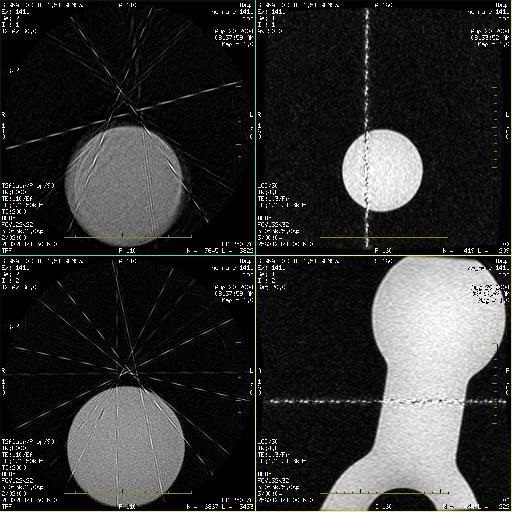

Crinkling

The crinkling on PROPELLER acquisitions can be caused by:

- The wrong ETL. The wider the blade (determined by ETL), the more data for blade comparison and correction.

- This may appear in the superior slices. The most common cause is low ETL prescriptions.

- Increase the ETL.

| 1 | ETL is 20 (TE = 90) |

| 2 | ETL is 28 (TE = 126) |

- Extreme patient movement

- Patient movement during any acquisition will result in sub-optimal images. In PROPELLER, the image may be captured at an angle.

- Increasing the ETL may result in better motion reduction, but as with all motion-induced artifacts, eliminating patient movement is the best solution.

- Phase Wrap

Be sure the FOV fully contains the anatomy.